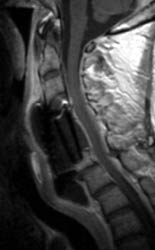

Sagittal T2 FSE (A), sagittal T1 pre (B) and post contrast

administration (C) show the graft with blooming artifact where the

plate exists anteriorly as well as the screw (lower portion of the image). The

susceptibility artifact of the screw shows its ventral positioning essentially

outside of the C7 vertebral body. Also, there is T2 hyperintense fluid

surrounding the surgical site with the graft material is now surrounded by

nonenhancing mixed signal intensity material, predominately hypointense on T1

and hyperintense on T2, possibly suggesting some blood products. There is

enhancement in both the anterior and posterior epidural spaces. The distal end

of the fixation plate with the screw in the C6 vertebral body appears now

displaced anteriorly and there is significant prevertebral soft tissue swelling.

Also, this fluid- like material surrounding the bone graft appears to cause some

narrowing of the spinal canal, with some mild spinal canal stenosis.